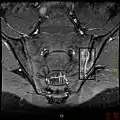

If these criteria still do not give a compelling diagnosis magnetic resonance imaging (MRI) may be useful.[23][24] MRI can show inflammation of the sacroiliac joint.

Options for earlier diagnosis are tomography and MRI of the sacroiliac joints, but the reliability of these tests is still unclear.

T1-weighted MRI with fat suppression after administration of gadolinium contrast showing sacroiliitis in a person with ankylosing spondylitis